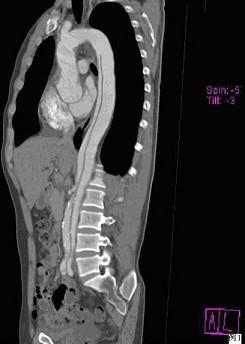

问题 请看一组主动脉的CT增强图像,正确的描述和结论是 ( )

选项 A、真腔较假腔小 B、真假腔之间线状低密度影为内膜片影 C、主动脉瘤 D、主动脉夹层 E、主动脉血栓

答案 ABD